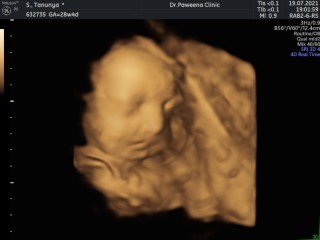

ซาวด์ตอน 28w 4d ตอนนี้ 30w แล้วค่ะ🥰